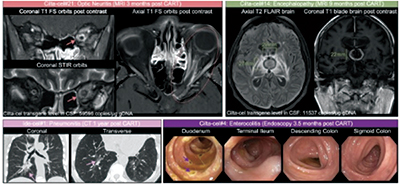

在西达基奥仑赛治疗者中,最常见的CirAE为脑神经麻痹(8%)、肠炎(5.6%)、帕金森病(4.8%)和关节炎(1.6%),而迟发性免疫效应细胞相关神经毒性综合征(ICANS)、脑病变和周围神经病变则较少见(各0.8%)。2例患者在西达基奥仑赛治疗下出现多次CirAE,其中1例74岁男性患者发生3例次不同的CirAE。ide-cel治疗中唯一被观察到的CirAE为肺炎。

CirAE与显著增高的非复发死亡率相关(HR=5.2,P=0.006),独立风险因素包括西达基奥仑赛治疗(OR=4.5,P=0.058)、输注后前14天绝对淋巴细胞峰值≥2.4×103个/微升(OR=4.3,P<0.001)及单采样本中CD4与CD8的比值>1(OR=2.6,P=0.048)。

在约14个月的中位随访中,1/3的CirAE患者死亡,其中2/3死于CirAE,西达基奥仑赛治疗患者的CirAE相关死亡率为4.8%。CirAE相关死亡和非CirAE相关死亡中的感染死因分别占60%和14%,这很可能为强化免疫抑制,尤其是大剂量类固醇所致。